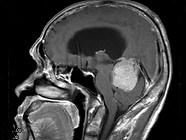

问题 男,61岁,头晕头痛伴行走不稳1月余,请根据所提供图像,选择最可能的诊断()

选项 A.胶质瘤 B.髓母细胞瘤 C.(天幕切迹缘)脑膜瘤 D.转移瘤 E.淋巴瘤

答案 C